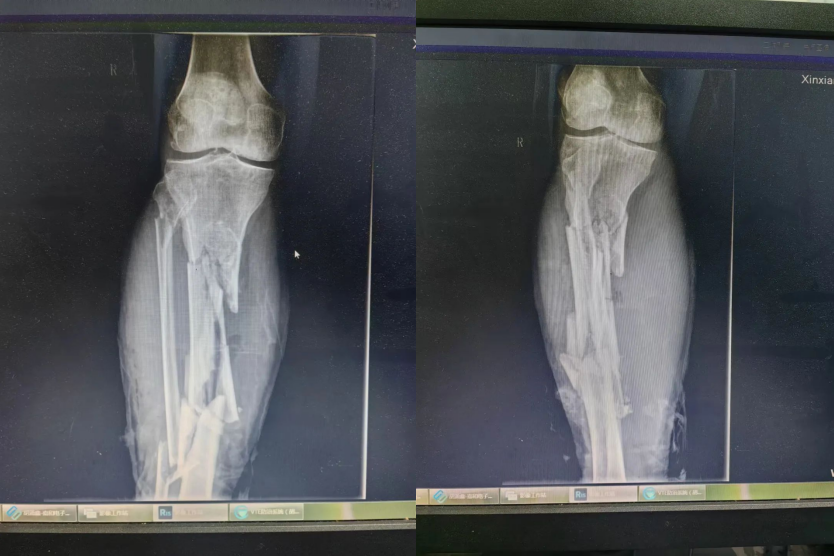

今年2月,患者賈師傅因車禍致右小腿粉碎性骨折,小腿長段粉碎,粉碎總長度達(dá)到26CM,隨即來我院就診,經(jīng)DR檢查,發(fā)現(xiàn)右脛腓骨粉碎性骨折。我院骨一科主任王鑫立即給予止血,肢具臨時(shí)固定。

后入住我院骨科二病區(qū)后,迅速制定了多學(xué)科診療方案?;颊哂颐劰菑钠脚_(tái)下到踝關(guān)節(jié)上方約6cm處粉碎性骨折,骨折端長26CM,合并兩處開放性傷口,軟組織挫傷嚴(yán)重,彩超檢查顯示肢淺靜脈血栓形成。

在做好充分術(shù)前準(zhǔn)備后,濾器置入成功,創(chuàng)傷團(tuán)隊(duì)為賈先生行脛骨長段粉碎骨折四軸伊氏架不切開復(fù)位外固定術(shù),術(shù)中置入多枚2.0無菌骨牽引針,應(yīng)用環(huán)形外固定架牽引復(fù)位骨折,全程不切開,出血少,固定牢靠,術(shù)后病人即可跟進(jìn)抗凝治療,術(shù)后三天順利下地行走。